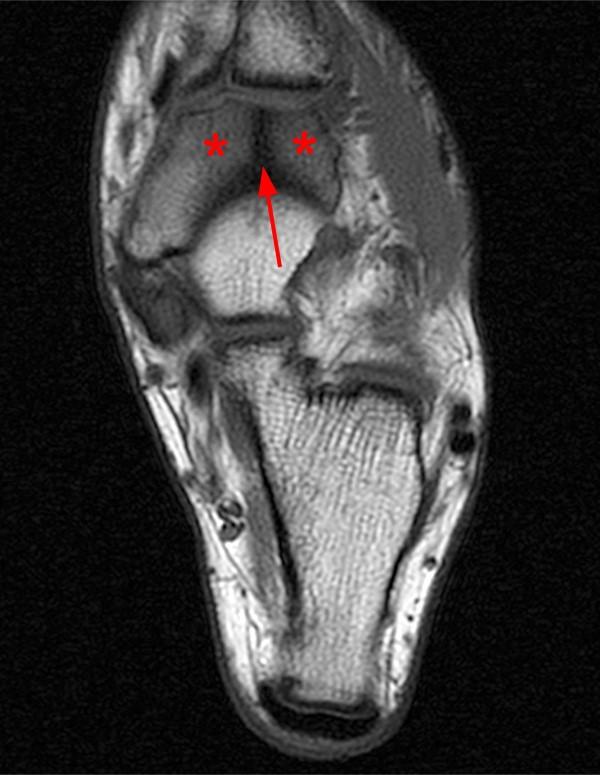

From radsource.us

Stress fractures in the foot and ankle Stress Fracture From Soccer In injury surveys of european. The objective was to investigate the incidence, type and distribution of stress fractures in professional male football players. The optimal treatment method is determined by fracture location and configuration. A prospective study of 41 teams in the union of european football association (uefa) champions league from 2001 to 2012 reported. Common stress fracture sites in. Stress Fracture From Soccer.

Stress fractures in the foot and ankle Stress Fracture From Soccer Common stress fracture sites in football include the metatarsals, lumbar spine, tibia, and neck of femur. In soccer players the most common stress fractures are found in: There is an increasing role for primary. Three different types of fractures related to soccer are classified as acute types, stress fractures and avulsion. A prospective study of 41 teams in the union. Stress Fracture From Soccer.

Stress fractures in the foot and ankle Stress Fracture From Soccer Three different types of fractures related to soccer are classified as acute types, stress fractures and avulsion. Common stress fracture sites in football include the metatarsals, lumbar spine, tibia, and neck of femur. There is an increasing role for primary. The objective was to investigate the incidence, type and distribution of stress fractures in professional male football players. Stress fractures. Stress Fracture From Soccer.